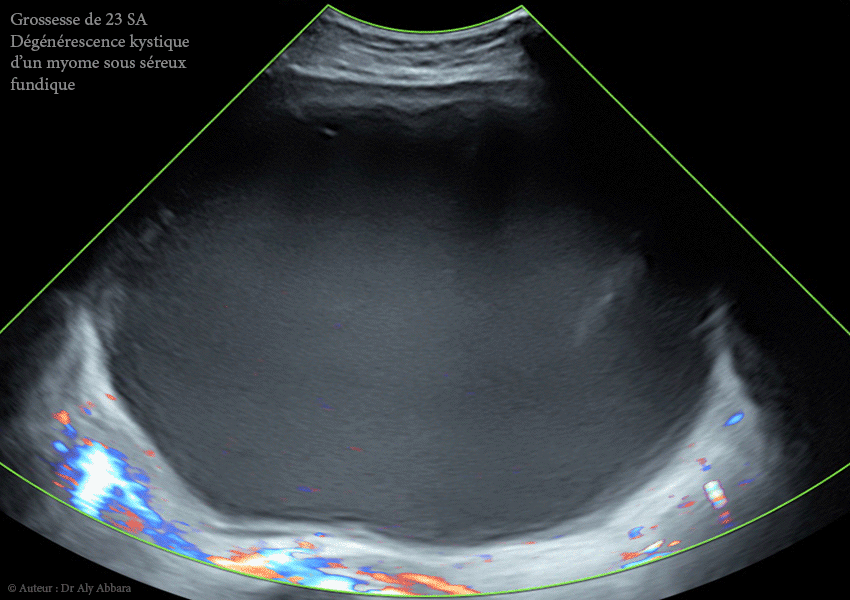

Images échographiques et séquences vidéo montrant une grossesse intra-utérine évolutive de 23 SA survenant au sein d'un utérus porteur d'un myome sous-séreux fundique (classe 7 de la classification FIGO 2011).

• Il s'agit d'un volumineux myome de 153 x 176 x 136 mm de diamètre, soit = 1904 cm3, découvert fortuitement lors de la première échographie de datation (à 10 SA puis à 12 SA), chez une jeune femme, primipare de 31 ans.

• On remarque échographiquement que ce myome qui présentait à 17 SA, dans sa partie centrale, de nombreuses zones liquidiennes enkystées de nécrobiose aseptique,

à 23 SA ce phénomène de (dégénérescence kystique du myome utérin) est devenu presque total : le myome a bien augmenté de volume (1904 ml contre 952 cm3 à 12 SA, soit le dédoublement de volume) ; il apparaît comme une énorme formation kystique à contenu trouble, hypoéchogène avec des plages d'aspect nuageux de résidus flottant (nécrotiques).

• Symptômes : douleurs abdomino-pelviennes épisodiques.

• À 23 SA : dégénérescence kystique quasi totale (1904 ml).